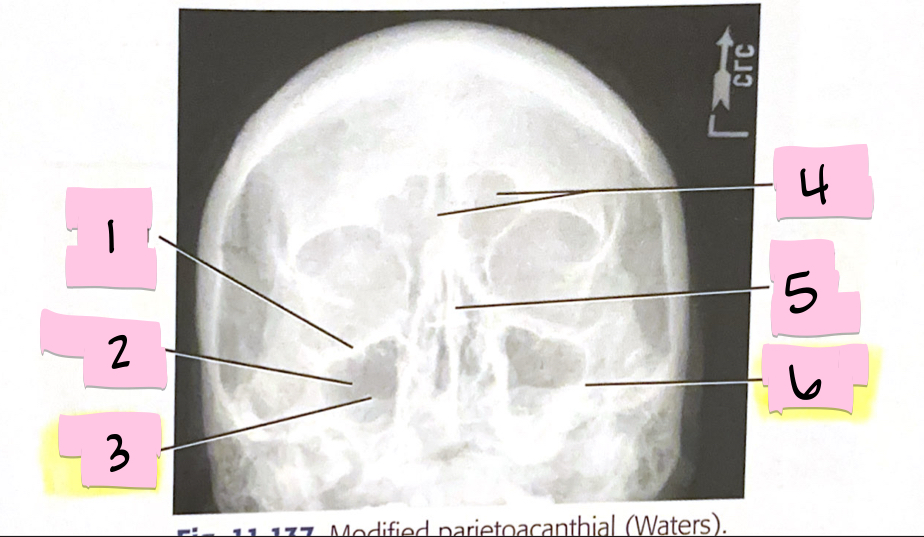

What is 1 pointing to?

Inferior orbital margin

What is 2 pointing to?

Maxillary sinus

What is 3 pointing to?

Petrous ridge

What is 4 pointing to?

Frontal sinuses

What is 5 pointing to?

Bony nasal septum

What is 6 pointing to?

Petrous ridge